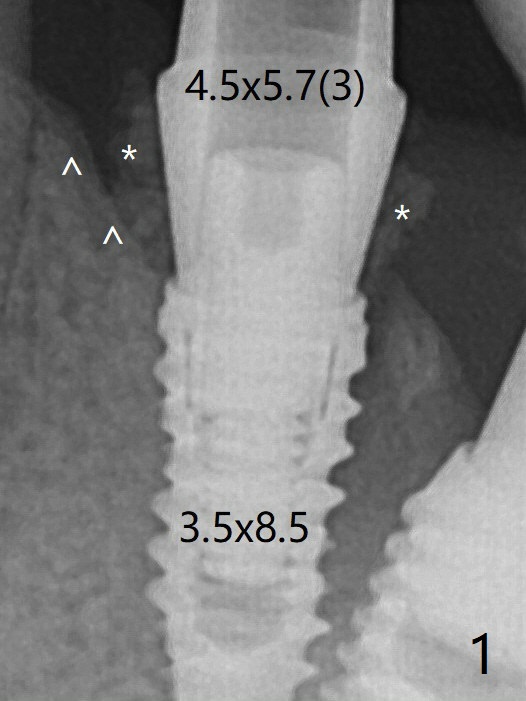

尽管术后即刻牙槽嵴放置粘性骨粉(图一:*),术后4个月远中牙槽嵴稍微下降(图五:*)。